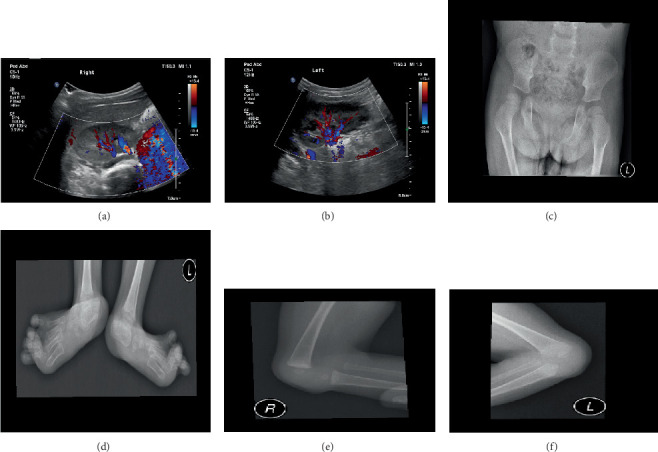

生殖髌骨综合征(GPS)是一种罕见的遗传性疾病,其临床表现包括髌骨缺失、精神运动迟缓、先天性下肢屈曲畸形和泌尿生殖系统异常。一名五岁女童到牙科学院诊所作例行牙科检查。体格检查显示明显的表型特征,特别是宽缩略图和肢体皱纹,而面部外观在正常范围内。出生时,患者表现为畸形畸形的内翻足,生殖器异常,双侧肾积水和肝肿大。随后的MRI评估显示双侧股骨滑车发育不良伴外侧髌股脱位,伴明显的胫骨旋转和垂直距骨。此外,双侧后脚外翻畸形和第一跖趾关节屈曲畸形也被注意到。Sanger测序的分子分析鉴定了KAT6B基因的一个从头杂合无义突变(c.4117, p.Glu1373Ter)。口腔检查显示临床牙冠缩短,乳牙无龋,乳牙(Cs)和第二磨牙(Es)的萌牙延迟。x线评估显示现有的初级e和门牙延迟出牙。本报告阐明了GPS与口腔表现之间的潜在联系,特别强调了原发性Es的延迟爆发。由于缺乏针对该综合征的口腔和牙齿表现的出版物,因此该临床病例有助于诊断,尽管不是具体的。

Genitopatellar syndrome (GPS) is a rare genetic disorder characterized by a spectrum of clinical manifestations including the absence of patellae, psychomotor retardation, congenital flexion deformity of the lower limbs, and genitourinary abnormalities. A 5-year-old female presented to the Faculty of Dentistry Clinic for a routine dental examination. Physical examination revealed distinctive phenotypic features, notably wide thumbnails and limb wrinkling, while facial appearance appeared within normal limits. At birth, the patient exhibited dysmorphic clubfoot, genital anomalies, bilateral hydronephrosis, and hepatomegaly. Subsequent MRI evaluation disclosed bilateral dysplastic femoral trochlea with lateral patellofemoral dislocation, accompanied by marked tibial rotation and vertical talus. Additionally, bilateral hindfoot valgus deformity and first metatarsophalangeal joint flexion deformity were noted. Molecular analysis using Sanger sequencing identified a de novo heterozygous nonsense mutation (c.4117, p.Glu1373Ter) in the KAT6B gene. Oral examination revealed shortened clinical crowns, absence of caries in the primary teeth, and delayed eruption of the primary canines (Cs) and second molars (Es). Radiographic assessment demonstrated existing primary Es and incisors with delayed eruption. This report elucidates a potential association between GPS and oral manifestations, particularly highlighting delayed eruption of primary Es. Since there is a scarcity of publications addressing the oral and dental manifestations of the syndrome, this clinical case contributes, albeit not specifically, to the diagnosis.